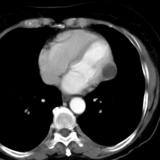

Part'l absc peric CT

Date: 07/23/2006

Views: 3171